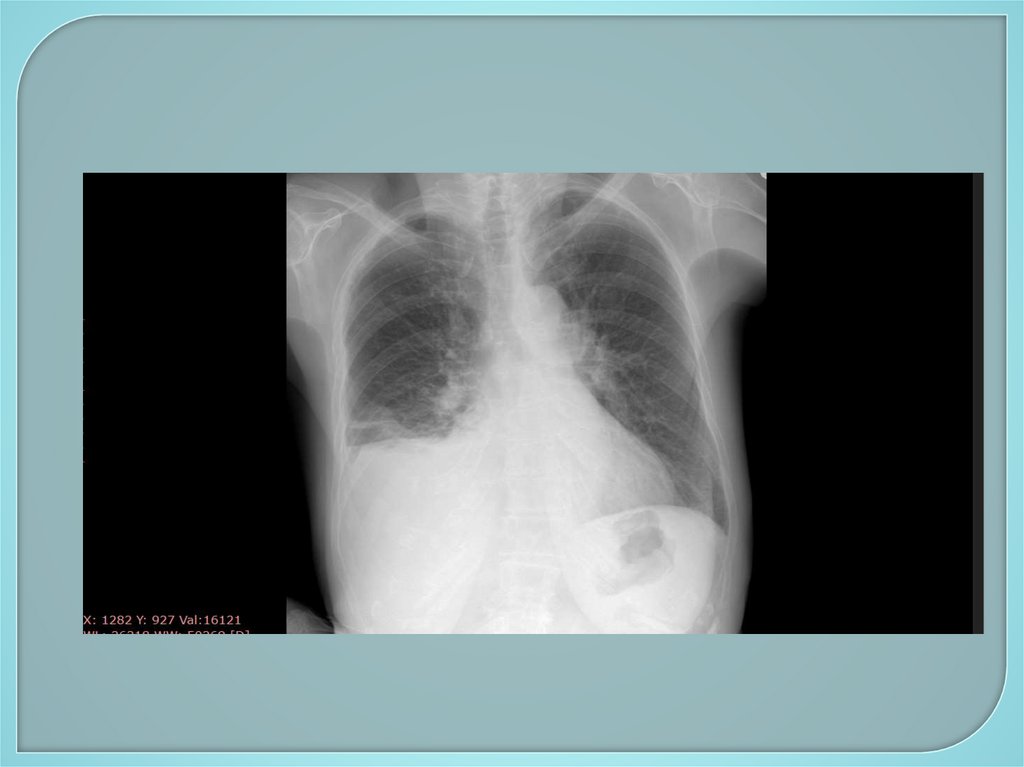

101. Дополнительное обследование

Инструментальные методы:

1. Рентгенологические методы –

рентгенография грудной клетки,

флюорография, бронхография,

компьютерная томография